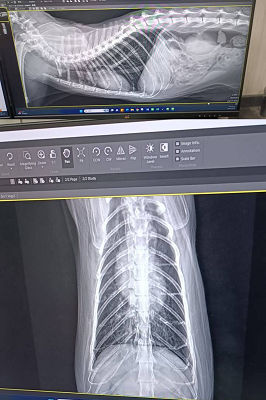

原本是先讓乖豹再留在台北安養之家觀察一小段時間,希望確定健康無虞後,再讓他回到熟悉的大湖安養之家,但在2021年1月,照護員回報乖豹食慾體重都有漸降,1月23日呼吸看來急促,立刻約診沐恩醫院檢查,檢查結果,體溫40.3度,超音波及X光檢查發現胸腔有不明團塊及胸水,給予鎮定後抽出了有膿的胸水,當天辦理住院打泰寧抗生素針,醫師研判是嚴重的細菌感染和發炎造成膿胸,住院2天時,紅血球有持續降低的情況,血容比低到21,1月25日放置胸管引流、沖洗胸腔並引流膿水,每日都需要血檢及沖洗胸腔,在狀況嚴重會需要開胸手術移除胸腔中的膿包及清創,可能會需要輸血,幸好乖豹的食慾精神都有逐漸變好、血容比也有慢慢回升,至2月4日胸管沖洗出都已是乾淨的水,食慾精神也都穩定,醫師認為已可出院自行照護醫療,因治療剃掉肚子一大片毛的乖豹,讓大家很心疼,怕他冷為他穿上可愛又保暖的衣服,也每天準備好多好吃的罐罐幫他補身體,至2月17日回診的X光檢查,原本住院時胸腔有一大一小兩個團塊已經都不見了,這樣表示大團塊只是膿包,所以吃了抗生素就消失了,3月17日再回診,血檢結果都有很好的進步,體重也有回升,膿胸的危機已經解除,只要三個月後再回診拍X光及追蹤血檢即可。